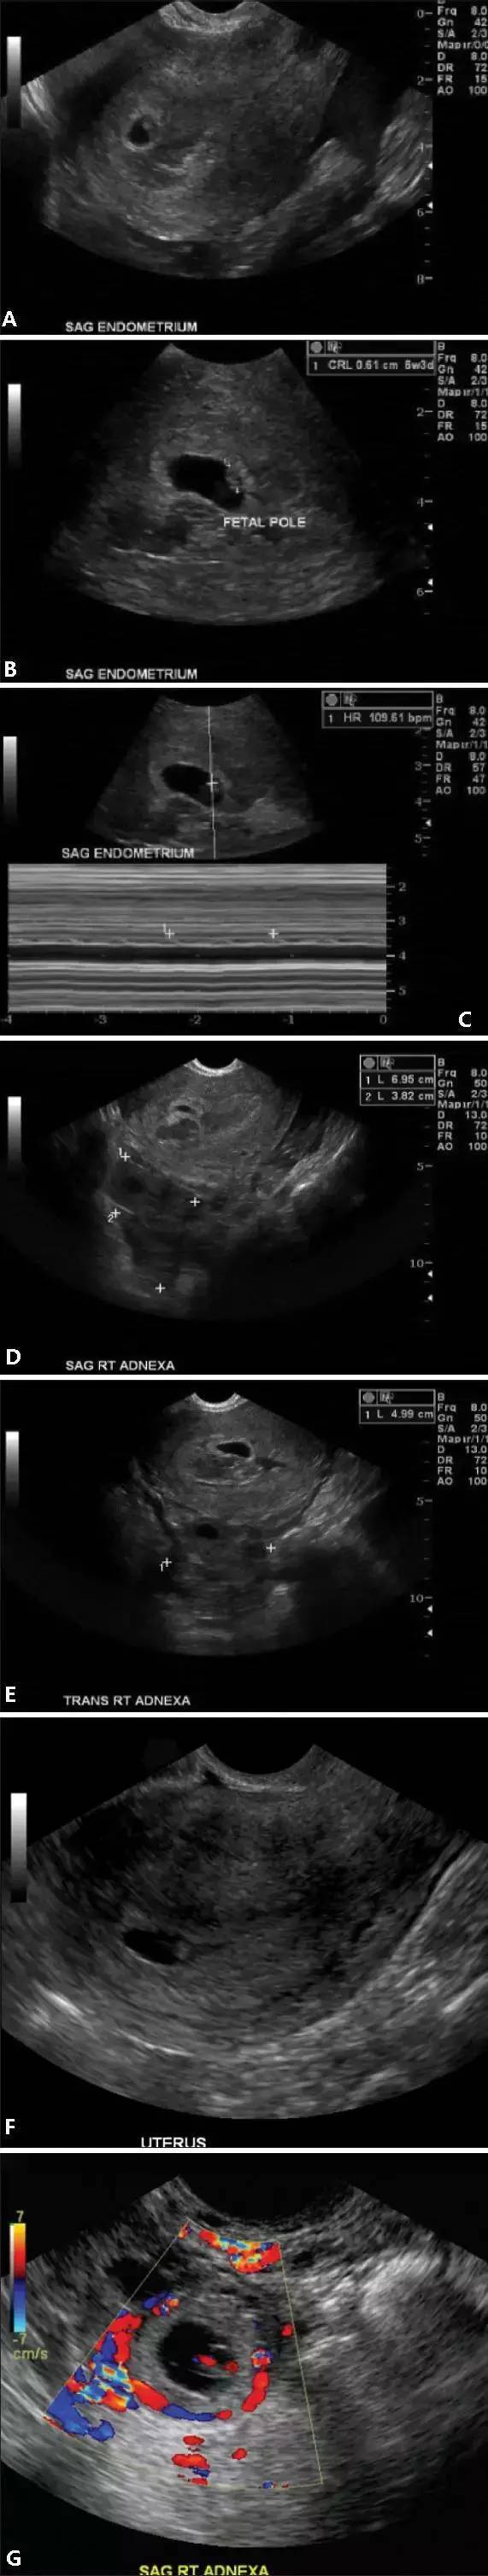

圖 2 宮頸異位妊娠。經陰道超聲矢狀面(A)和橫切面(B)圖像顯示宮頸內的異位妊娠。子宮直腸陷窩內可見游離液體

圖 3 宮頸流產?;颊咭蜿幍懒餮腿爰痹\科,矢狀面(A)和橫切面(B)圖像顯示宮頸內的流產過程,1 周前超聲顯示宮內正常妊娠

圖 5 異位雙胎妊娠聲像圖。橫切面圖像(A-C)顯示宮腔內一 6 周大小的妊娠囊,其后方可見部分混合回聲積液(A);矢狀面(D)和橫切面(E)圖像顯示右側卵巢增大,回聲不均質,其內可見一小囊樣結構。根據聲像圖和臨床表現,診斷為異位雙胎妊娠;圖 F 和圖 G 顯示另一例右側附件區的異位雙胎妊娠